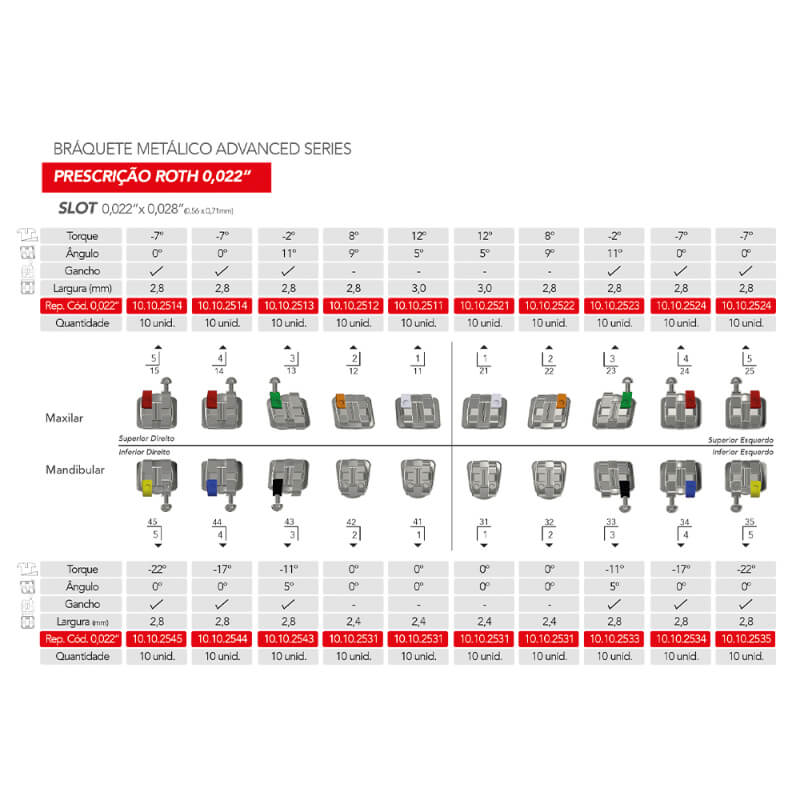

- Identificación por colores